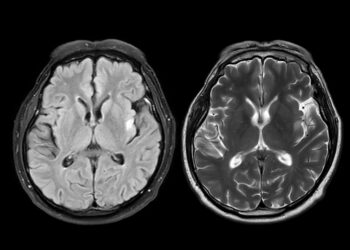

Skaityti daugiauDetailsMetachromatinė leukodistrofija (MLD) yra reta paveldima liga, kurios metu pažeidžiama centrinės (smegenų ir nugaros smegenų) bei periferinės nervų sistemos baltoji...

Skaityti daugiauDetailsMetabolinė encefalopatija – tai būklė, kai dėl tam tikrų organizmo sutrikimų neveikia smegenys taip, kaip turėtų. Dažniausiai šie sutrikimai susiję...